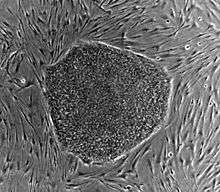

Somatic cell nuclear transplantation has become a focus of study in stem cell research. The aim of carrying out this procedure is to obtain pluripotent cells from a cloned embryo. These cells genetically matched the donor organism from which they came.This gives them the ability to create patient specific pluripotent cells, which could then be used in therapies or disease research.[3]

Embryonic stem cells are undifferentiated cells of an embryo. These cells are deemed to have a pluripotent potential because they have the ability to give rise to all of the tissues found in an adult organism. This ability allows stem cells to create any cell type, which could then be transplanted to replace damaged or destroyed cells. Controversy surrounds human ESC work due to the destruction of viable human embryos. Leading scientists to seek an alternative method of obtaining stem cells, SCNT is one such method.